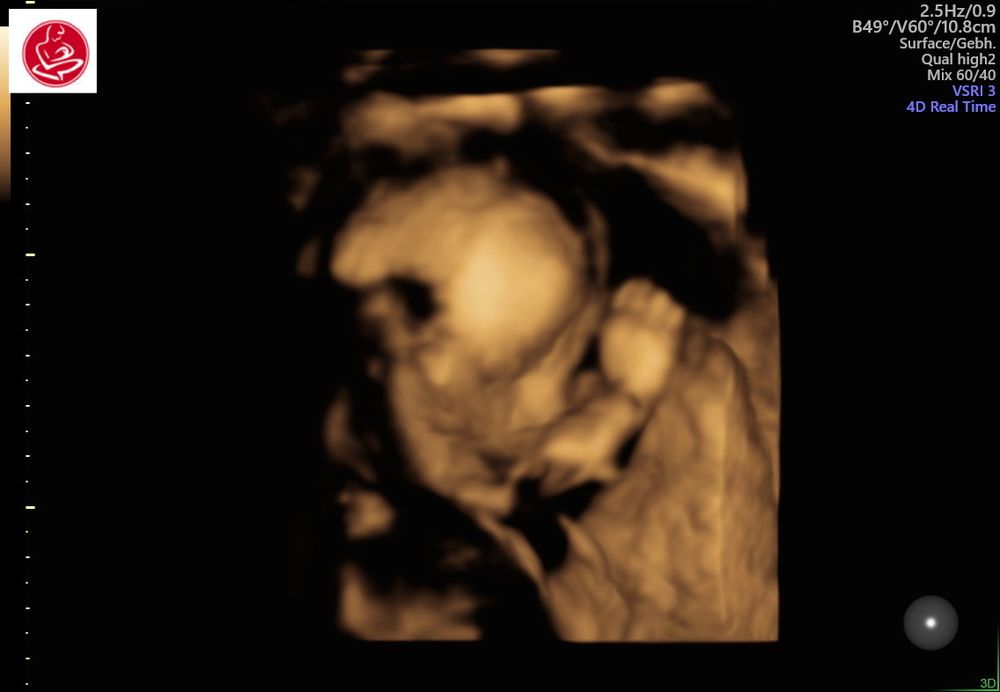

Неожиданный поворот при узи на 21-й неделе

ЭкваторСегодня был первый (второй) скрининг, срок 20.5. До этого дня очень переживала за малыша,почему то загоняла себя мыслями а вдруг что не так, всё таки возраст, который в группе риска. Но

к счастью всё в полном порядке. Опережаем почти на две недели (по замерам),вес 473 грамма. Ну и собственно сам нежданчик в том , что ждали ДОЧЬ, а дождёмся СЫНА😄 Узи делали каждые две-три недели и каждый раз мне подтверждали девочку, но сегодня я пошла к другому врачу, аппарат там шикарный был, там меня и огорошили😄. Но я не расстроилась, мне важно здоровье карапуза!) Для малыша уже давно всё куплено и в нейтральных цветах, так что слава богу менять не прийдется))Много таких историй слышала но не думала что сама с этим столкнусь😄